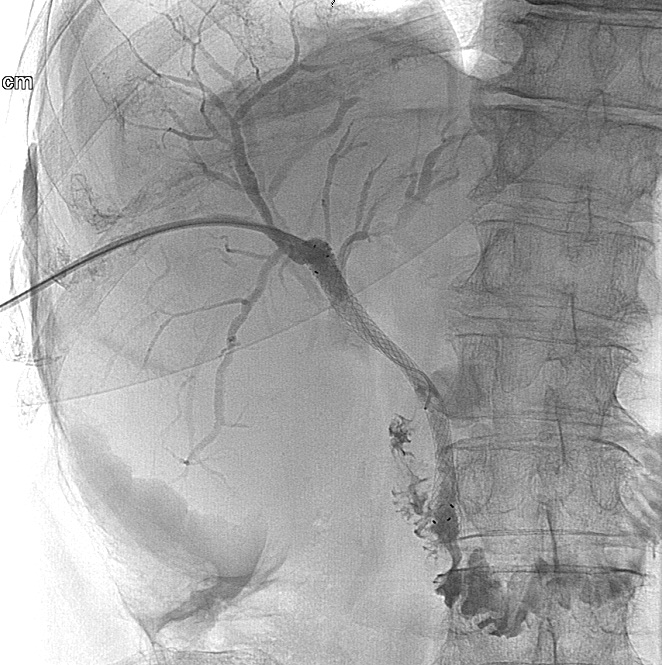

During this procedure X-ray or US is used to guide the insertion of a 22G (Chiba needle) from a right IX. or X. intercostals position into a dilated intrahepatic biliary branch. After the Chiba needle is well positioned the intra and extrahepatic biliary tree is filled with contrast material. (Figure 21.)

Under special circumstances – when the left side of the biliary branches is affected primarily - PTC can be performed from an epigastric entry towards the left lobe of the liver. (Figure 22.)

Image

Figure 21. – PTC (Percutaneous transhepatic cholangiography)

Figure 22. – PTC the puncture of the biliary branches of the left lobe